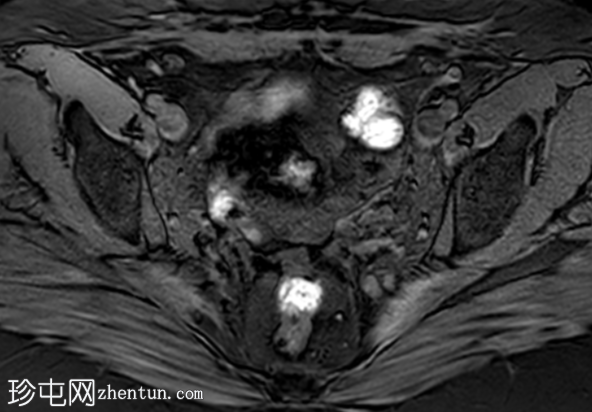

轴位T1加权像

增强脂肪抑制像

盆腔MRI显示左侧骶前区有两个小囊性病变,位于左侧附件的预期解剖位置。

病变在T2加权像上呈高信号,边界清晰,囊壁轻度增厚,光滑。在T1加权脂肪抑制像上,一个病变内部呈高信号,另一个病变呈低信号。静脉注射对比剂后,可见轻度周边囊壁强化,未见强化的实性成分。

未见扩散受限。病灶与邻近盆腔血管关系密切,无周围炎症改变、盆腔淋巴结肿大或游离液体的证据。

本例中,患者既往有双侧卵巢切除史,左侧附件预期位置出现小囊性病变,其中一个病变内含血性物质,且有轻度周边强化,支持卵巢残留组织的诊断。由于无扩散受限或侵袭性影像学特征,因此恶性肿瘤等其他诊断的可能性较小。